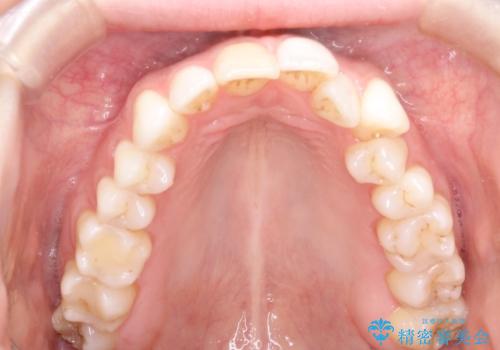

インビザラインによる非抜歯での八重歯の矯正

- 左上の八重歯と、上の歯のがたつきを主訴に来院されました。

上の奥歯を後方に移動させてスペースを作るのと、歯と歯の間をわずかに削り歯を並べる計画としました。

非常に強力的な患者様であったので、上下の正中も合わせ、ガタガタも改善することができました。